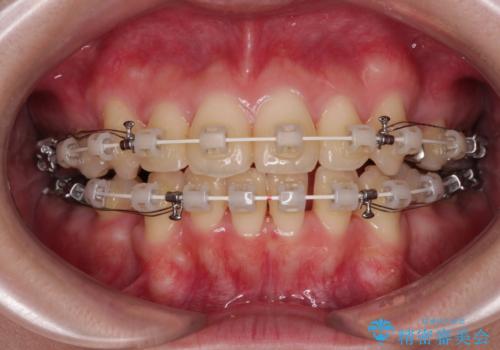

- 矯正装置

- 審美装置

- 1年11ヶ月